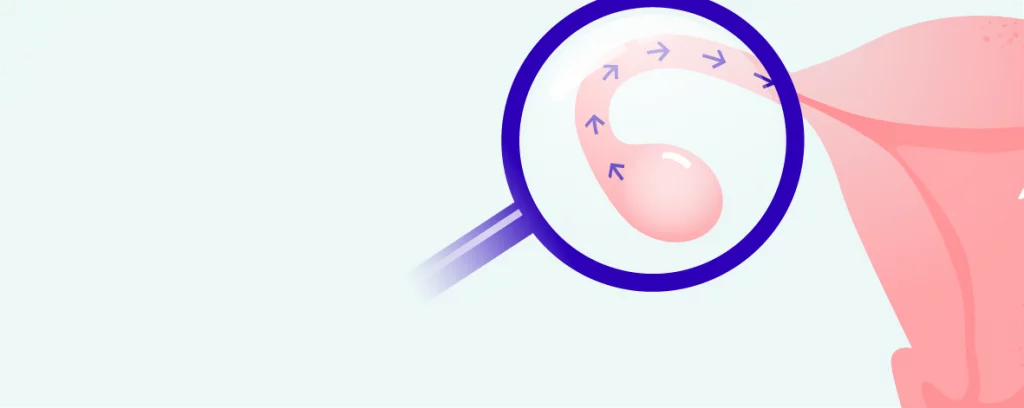

If the fallopian tubes are obstructed, there is little chance of natural conception. Even intrauterine insemination (IUI) is not the answer in this case. Conception is only possible with IVF, where the embryo is transferred directly into the uterus. For this reason, assessing fallopian tube patency is one of the basic tests for women who can’t conceive. There are a number of methods to test fallopian tube patency, but the simplest and most conclusive is ultrasound with a contrast agent (contrast-enhanced ultrasound).

We use the ExEm® Foam Kit for patency testing. Foam is created by mixing ExEm® gel and purified water, and this is used to fill the fallopian tubes. Ultrasonography images are then taken to determine tubal patency. Foam has much better visibility on ultrasound than, for example, a saline solution.

The patency and functionality of the fallopian tubes is vital in the reproductive process. The egg and sperm meet in the fallopian tube, which subsequently ensures that the fertilised egg travels to the uterine cavity, where the embryo implants (nests) and continues to grow.

In case of obstructed or dysfunctional fallopian tubes, the embryo may attach in the wrong place, resulting in an ectopic pregnancy. Completely blocked fallopian tubes are then the cause of infertility. The most common causes of blocked fallopian tubes are inflammation (e.g. ovarian inflammation, uterine inflammation, chlamydial inflammation), endometriosis or adhesions following inflammation or previous surgery in the abdominal cavity.